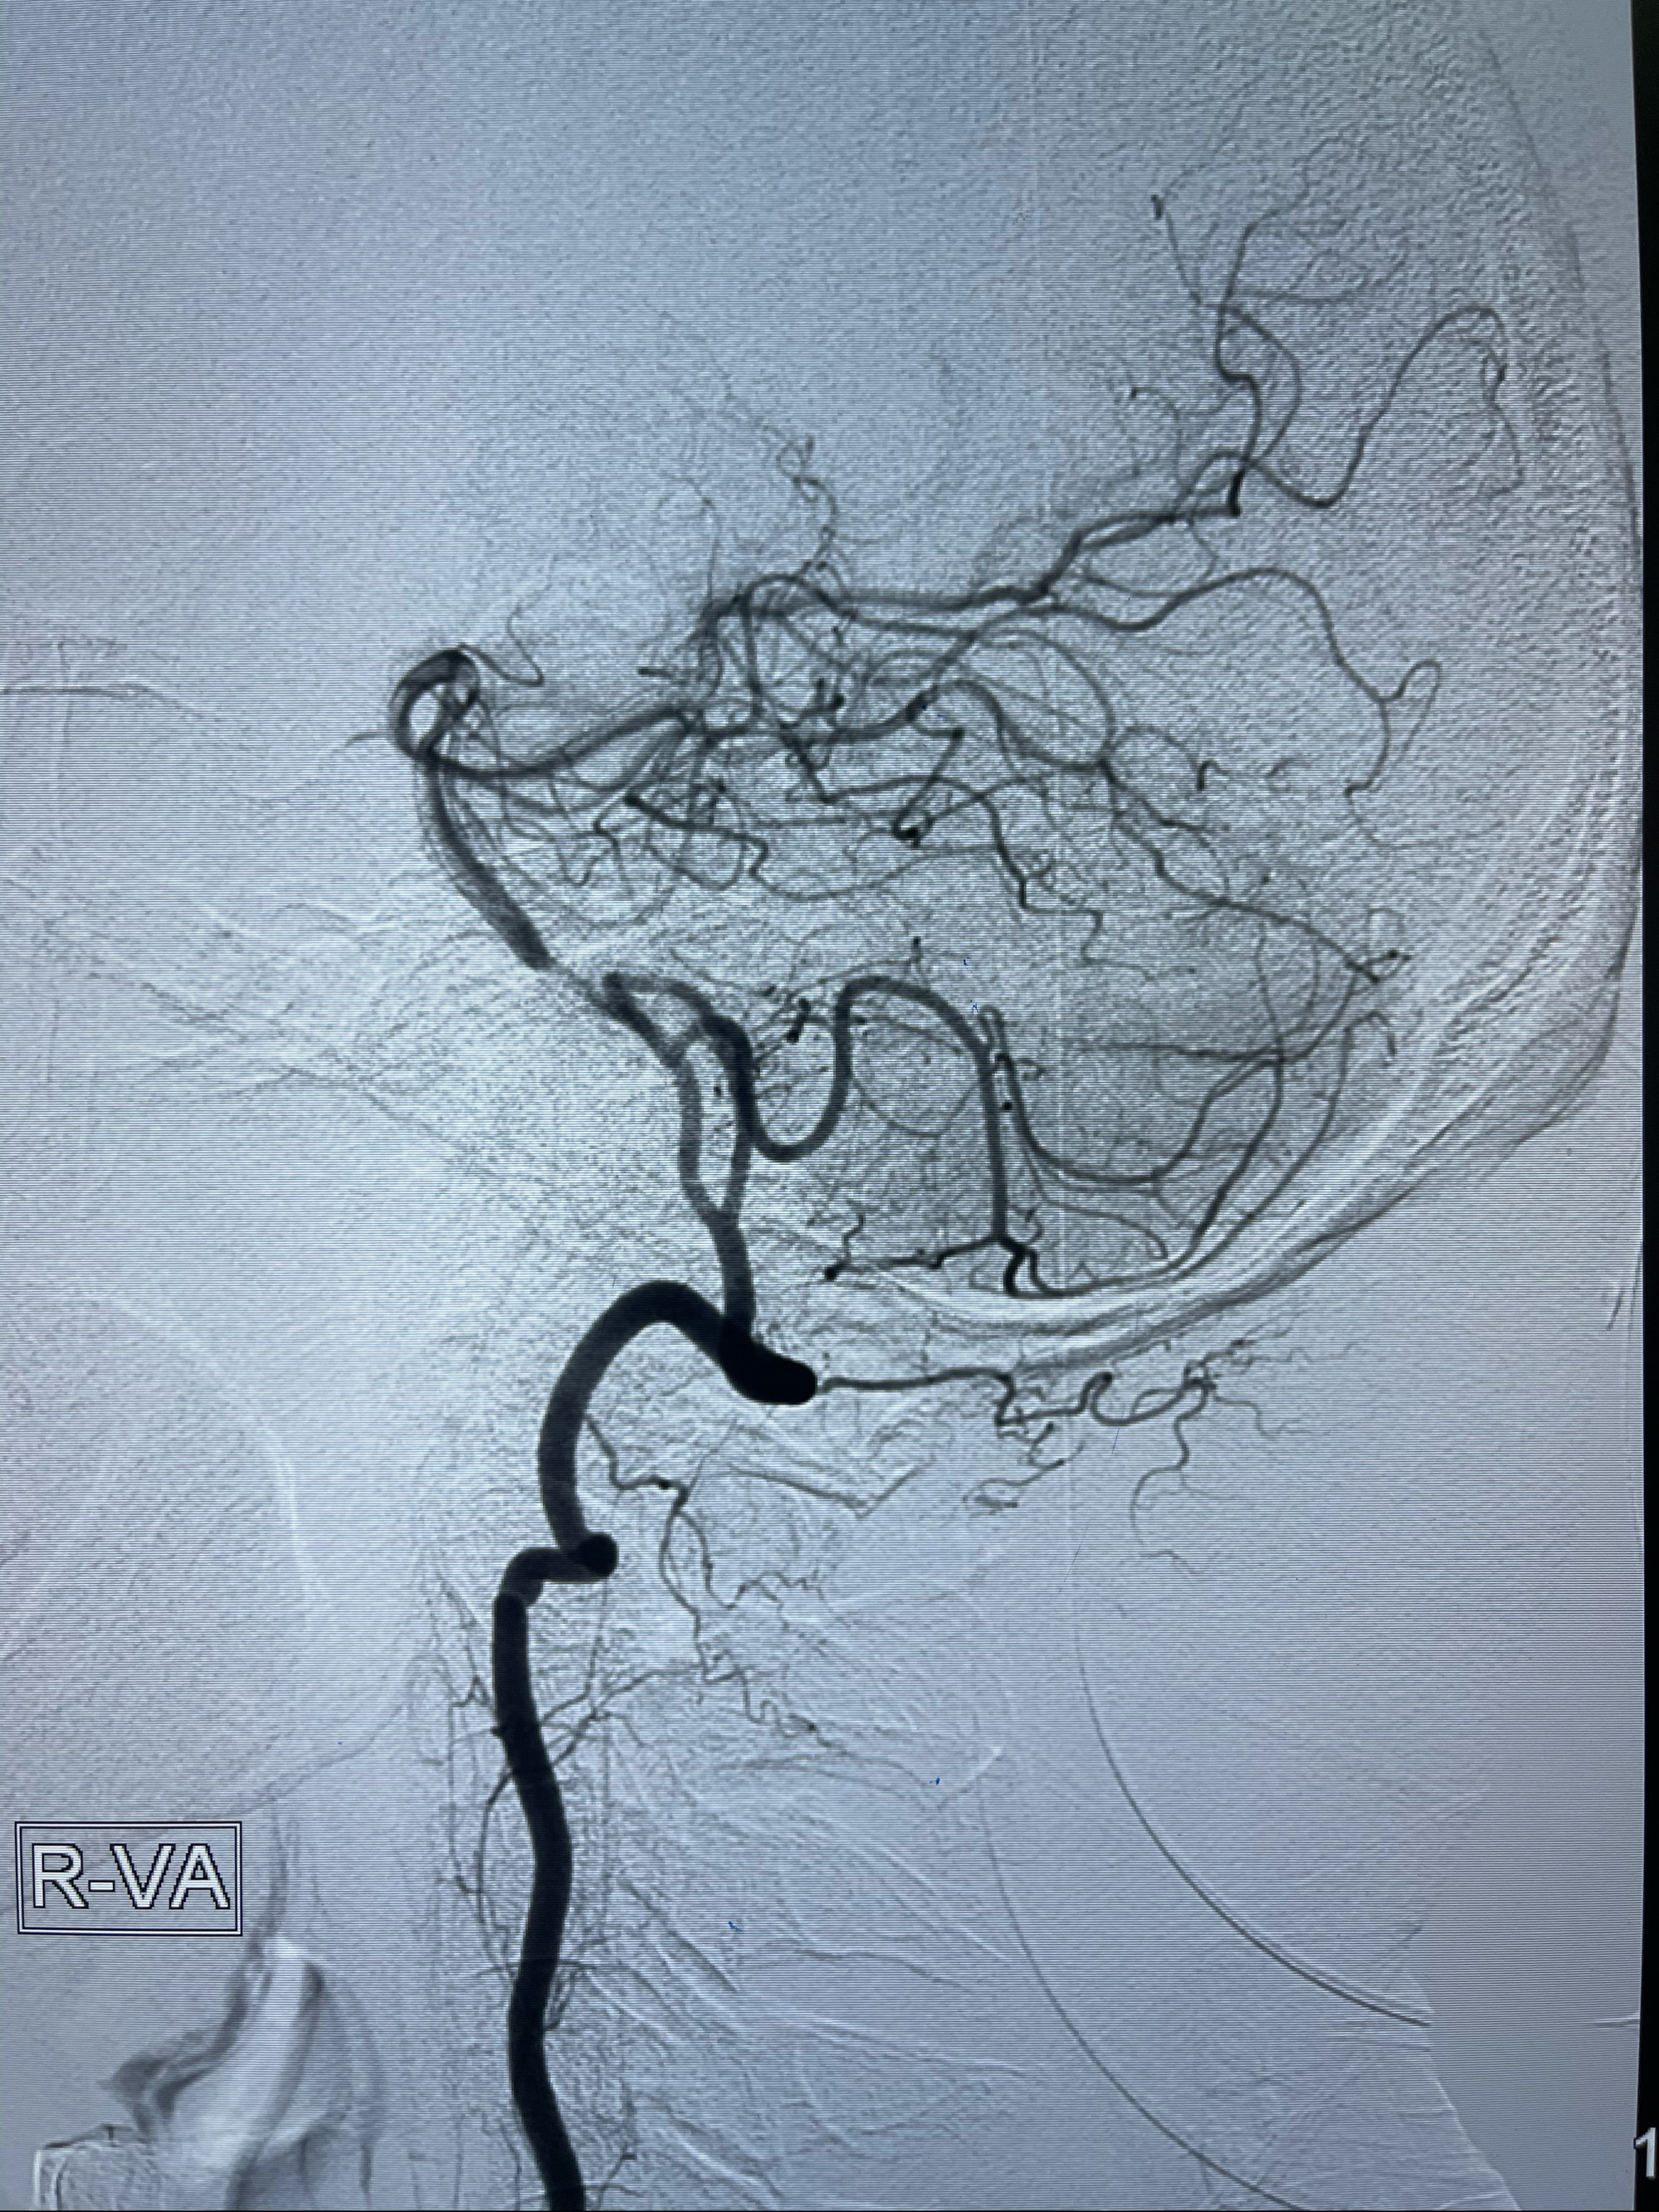

2021-03-08行全脑血管造影

2021-03-15全麻下多发动脉瘤支架辅助栓塞

右侧颈内动脉夹层动脉瘤Lvis5.5-20mm支架辅助栓塞

左侧椎动脉V4夹层动脉瘤多支架辅助栓塞:

工作角度造影